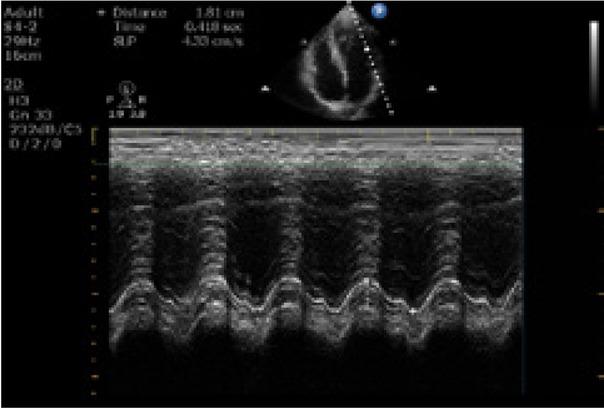

Volunteers who had given their consent were included in the study. After basic measurements, IVC and MAPSE measurements were performed with a phased array transducer (Mindray DC-60 Exp Ultrasound system, China) at 3.5–5 MHz in the B-mode scan. After the volunteer had rested for a while, IVC measurements were performed on the subxiphoid region, while the volunteer was in the supine position. By imaging the adjacency of the liver and heart through the subxiphoid window, the junction of the inferior vena cava and the left atrium was detected. A measurement was performed on the image obtained in the M-mode, approximately 2 cm distal from this part. Measurements were done, and the diameters of the vena cava in inspiration and expiration were recorded. A video recording was performed in the B-mode during at least three breathing cycles. Maximum IVC measurement was performed from one inner wall to the other inner wall during inspiratory and expiratory phases in the B-mode, where the edges of the IVC were clearly visible (Fig. 1). While the patient is in the supine position, to evaluate mitral annular plane systolic motion, which provides important information about the patient’s left ventricular functions, an M-mode tracing was obtained from the junction where the mitral annulus combines with the lateral free wall in the apical four-chamber view. In this tracing, two movements towards the apex were observed. The first forward movement was the systolic movement of the annulus, while the second positive wave was low amplitude and belonged to the atrium systole. Taking presystolic thinning as the baseline level in these two movements, the distance from baseline to peak gave information about the magnitude of systolic movement for systolic function (Fig. 2). Both the IVC and MAPSE measurements were repeated three times, and an average was calculated for the analysis. After the initial US measurements were completed, the volunteers were allowed to proceed to the blood donation procedures. Each procedure took 10–15 minutes. Following the IVC and MAPSE measurements and 450 mL blood donation, and after 10 minutes of rest, the initial measurement procedures were repeated without changing the body position of the volunteer, and vital signs measurements were recorded in the same way.

Fig. 2

Ultrasound image of MAPSE measurement